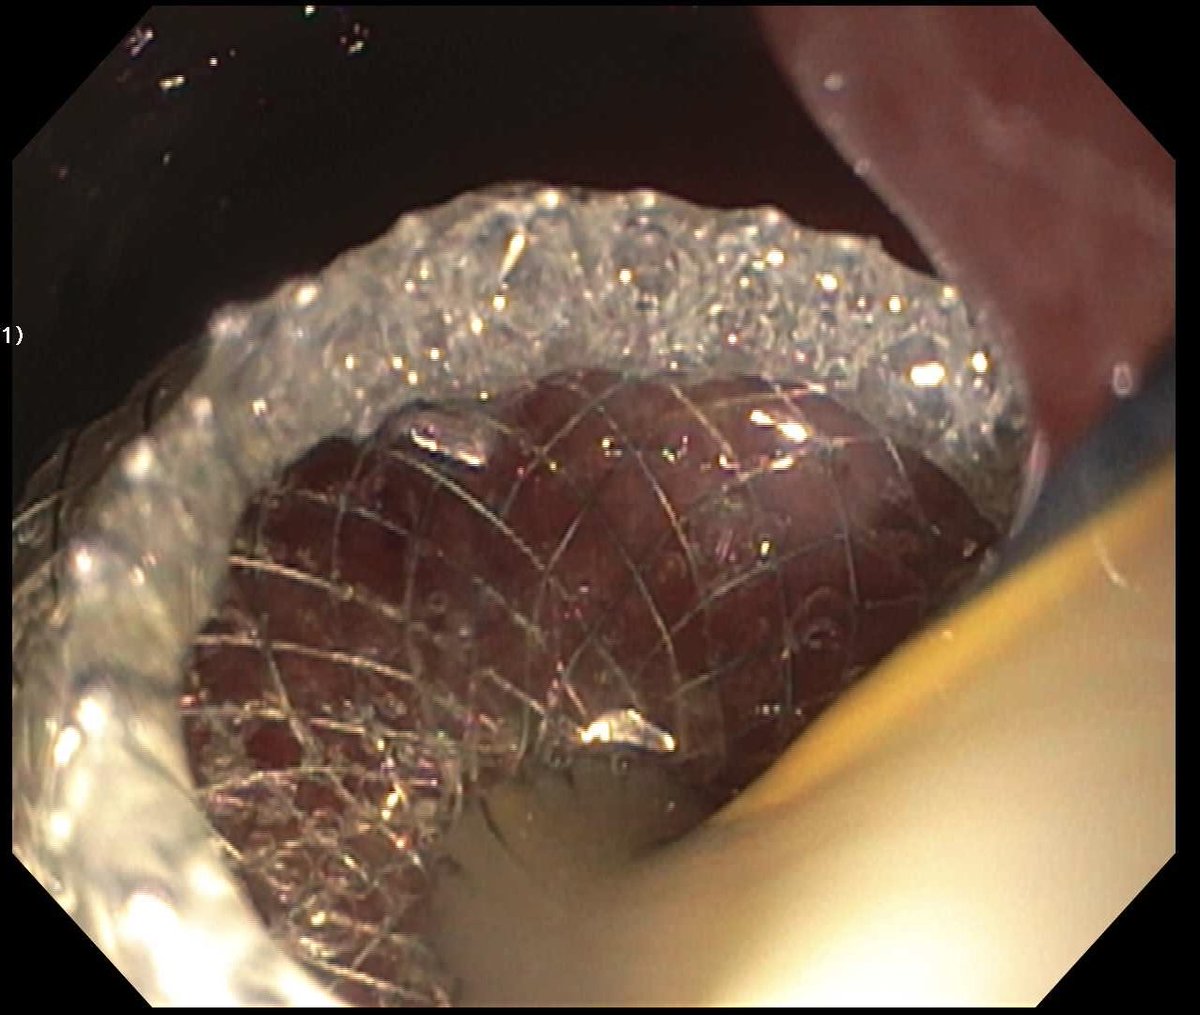

Biliary drainage via EUS-guided hepaticogastrostomy for distal MBO after failed ERCP. EUS continues to redefine what’s possible in GI intervention

Precision. Palliation. Progress.